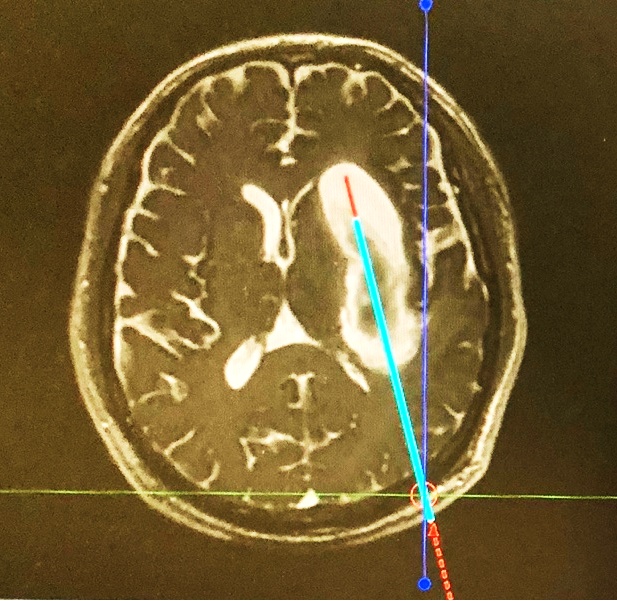

经过精密的术前准备与讨论,侯立军主任根据独创的国际创新理念与术式,为老杨实施了机器人辅助下枕部入路颅内血肿穿刺引流术。手术机器人的机械臂经过精准的计算与术前计划,准确的避开功能区,穿刺到达血肿,将血肿完全吸除。整个手术过程仅半小时,出血量微乎其微。

术前设计手术规划

左:术前设计的精准穿刺路径

右:术后可见血肿完全清除